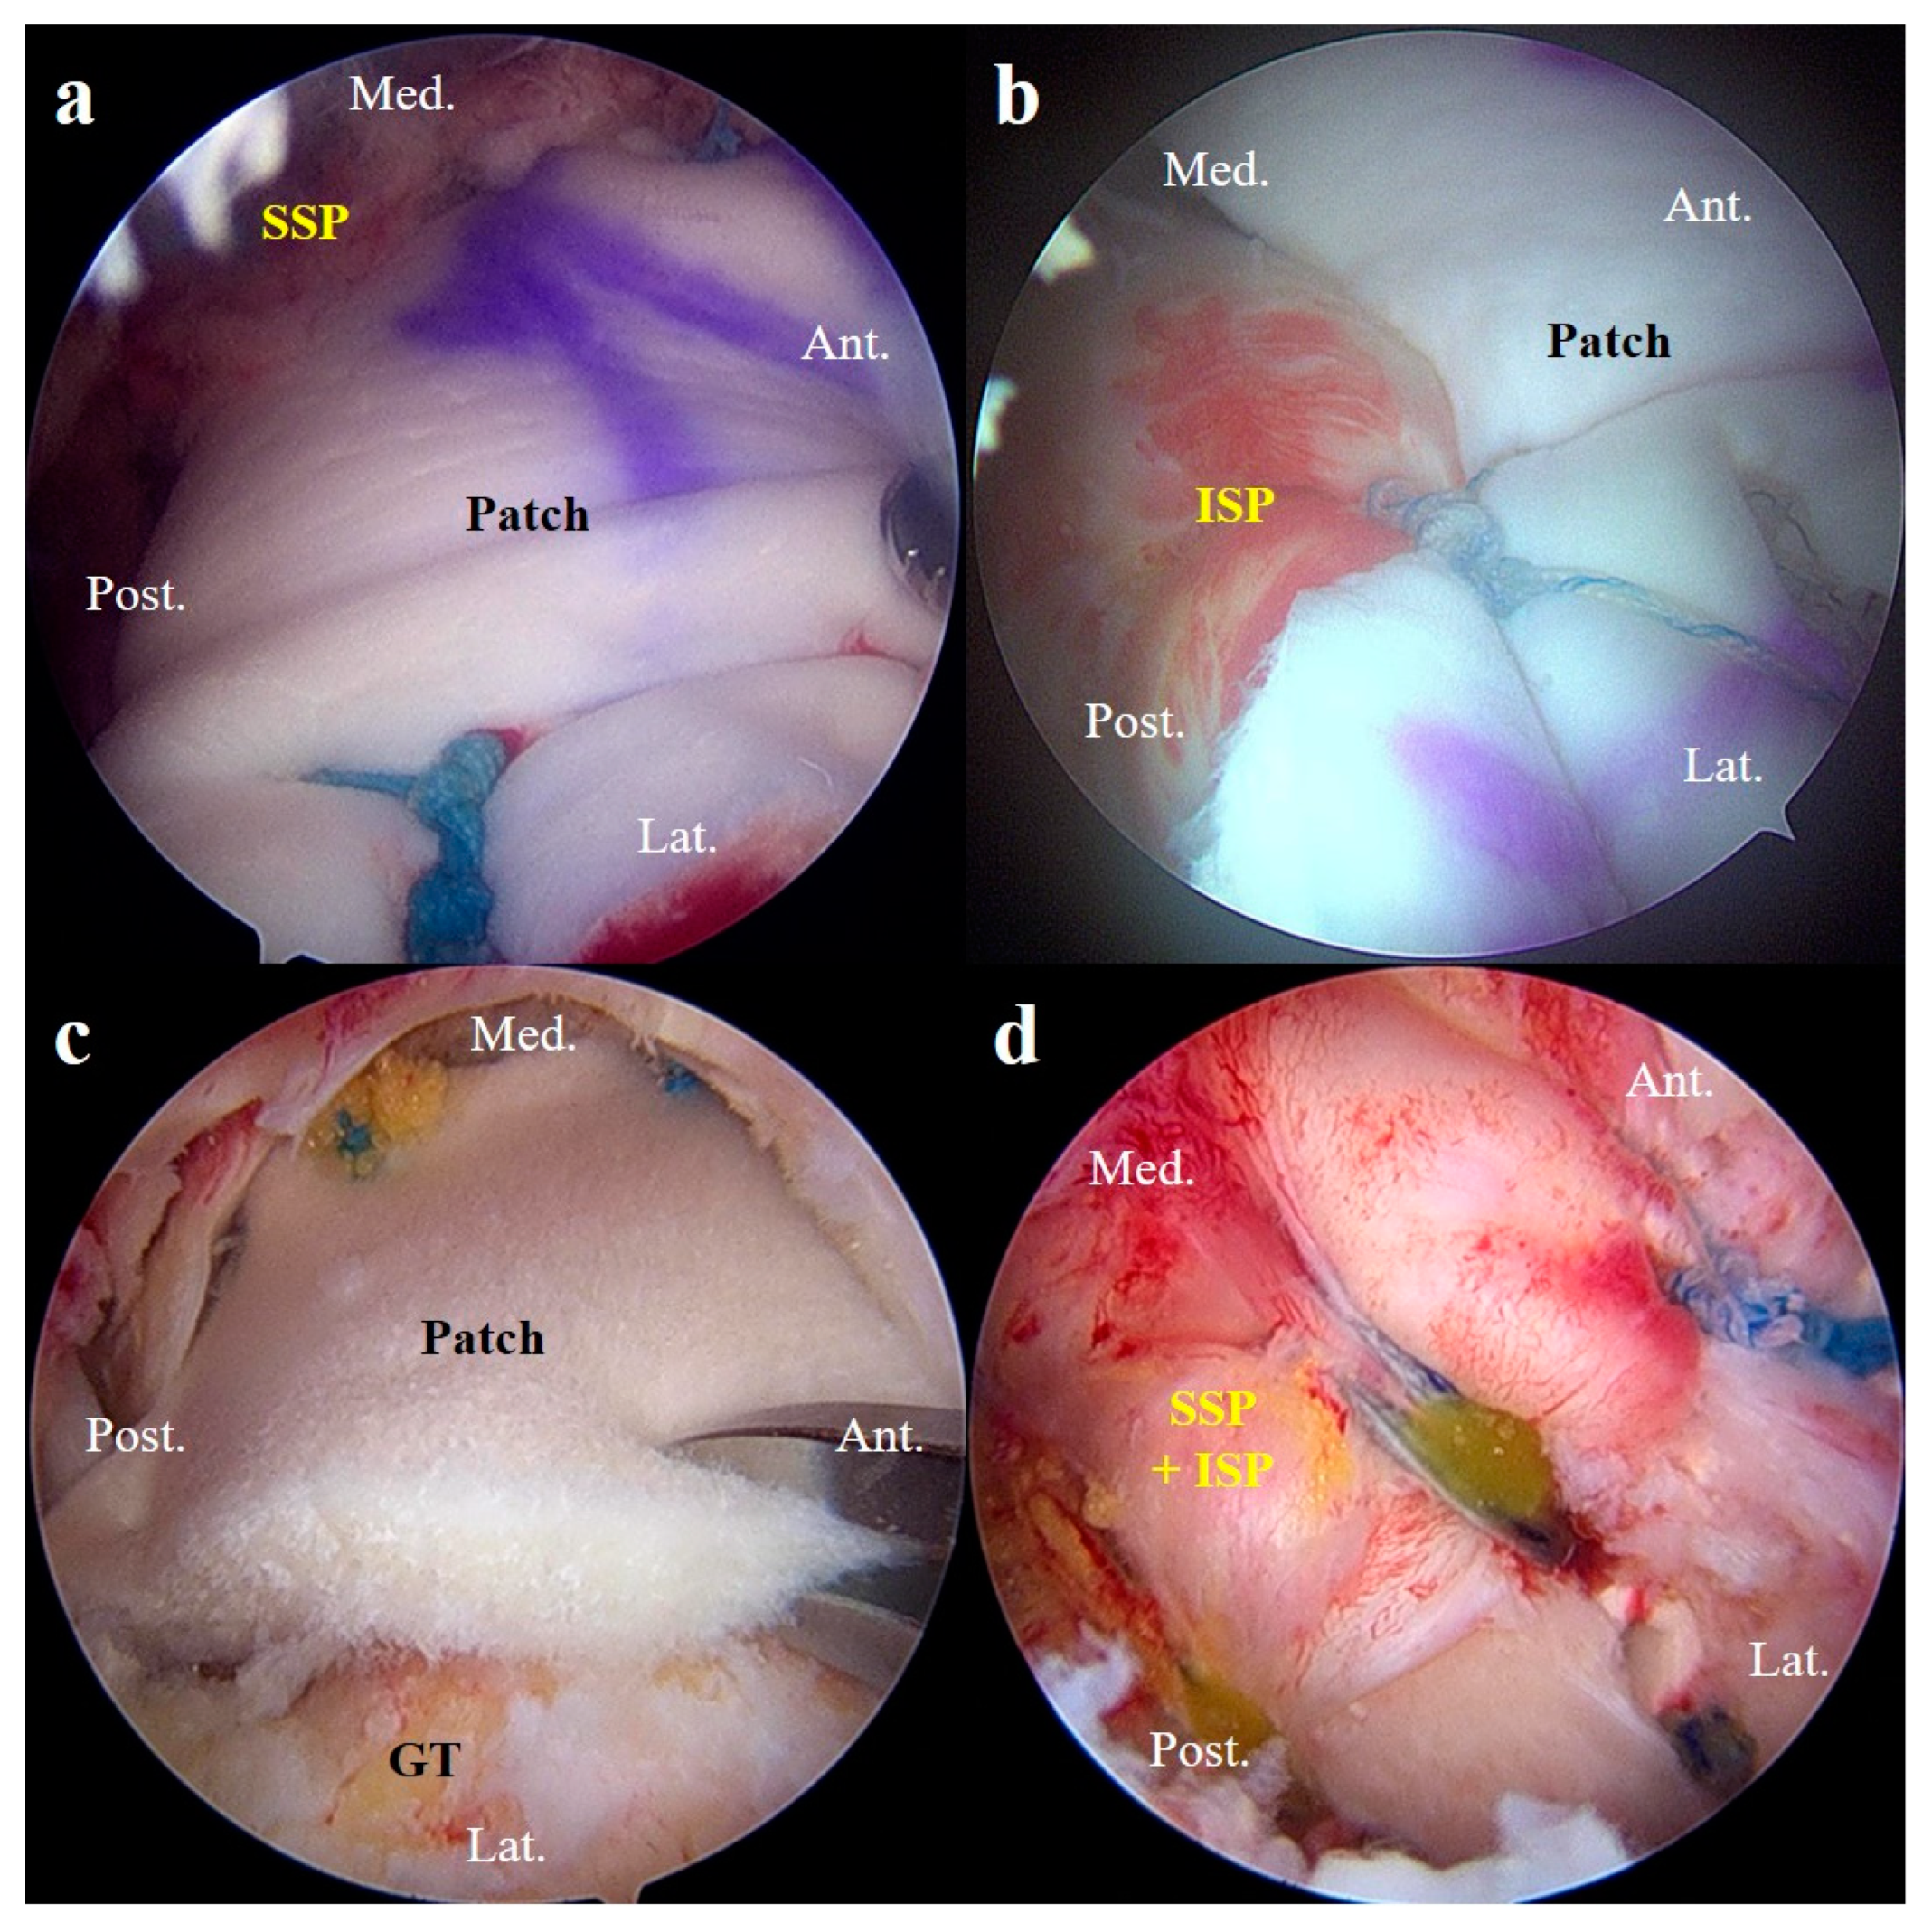

Reinforcement Techniques in Arthroscopic Repair of Large-to-Massive Rotator Cuff Tears: A Comparative Study of Superior Capsule Reconstruction and Patch Graft Augmentation

2. Materials and Methods

2.1. Patient Enrollment

3. Results

3.1. Patient Characteristics